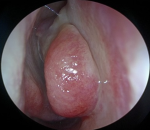

Examen clinique: endoscopie nasale: bombement du cornet moyen droit réduisant la lumière nasale, muqueuse intacte, sans signe inflammatoire (Figure 1).

Figure 1: image endoscopique préopératoire illustrant la concha bullosa droite géante